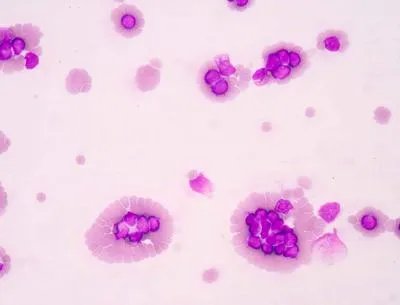

血小板减少性紫癜是什引起的

1、原发性血小板减少性紫癜在临床上分为两种类型,一种是急性,另一种是慢性。急性血小板减少性紫癜通常与病毒感染有关,比如感染风疹、麻疹、水痘等,也可能与感染流行性腮腺炎病毒有关。而慢性的血小板减少性紫癜患者通常与某种肝病有关,如之前患有肝炎,发病率会大大提升。

(1)可能与某种造血系统疾病有关,比如再生障碍性贫血、骨髓瘤、白血病等,也可能与恶性淋巴瘤、骨髓纤维化症等疾病有关,这些疾病发作容易引起贫血或者溶血,从而诱发血小板减少性紫癜。